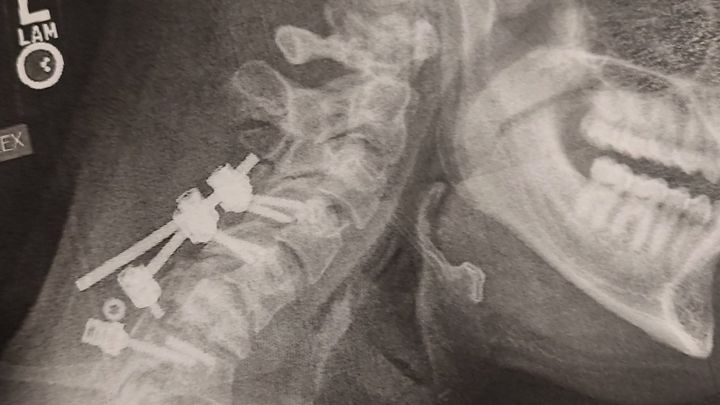

Seth has had surgery for a broken neck back in June 2025. His neck brace broke 3 times not even a month after his surgery, his recent X-ray on December 29th showed that the rod broke off the screw and has a curve starting in his neck, so he has to have surgery again sometime this month. He has not had any income so we are asking for help for his car insurance bill and keeping his phone on and just everyday living expenses food, hygiene products and some minor car repairs.